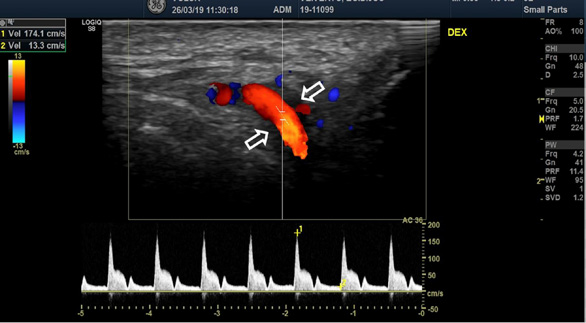

The blood test showed significantly increased CRP (208 mg/l), ESR (68 mm/h) and leucocytosis (12.30*10^9/l). Color-coded duplex sonography revealed the concentric hypoechoic thickness of the walls in both superficial temporal arteries, known as the ‘halo’ sign, which is a specific ultrasound finding in the case of GCA. The blood flow velocities of the superficial temporal artery were increased by approximately 200 cm/s bilaterally (Fig. 1 A, B).

Figure 1. Color-coded duplex sonography of the superficial temporal artery before the treatment (2019)

Color-coded duplex sonography revealed the typical ultrasound findings of temporal arteritis: the ‘halo sign’ as the dark area around the superficial temporal artery lumen probably due to arterial wall oedema (white arrows) with increased blood flow velocities on the right (A) and left (B) sides.